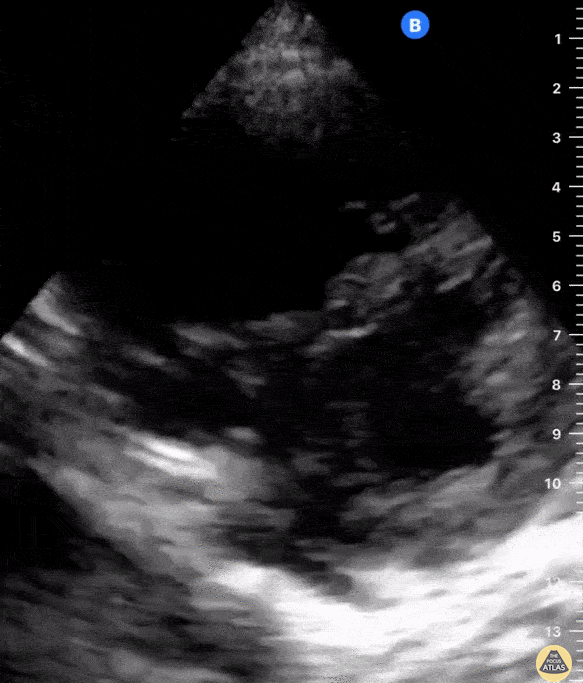

En vue A4C, le VG occupe deux tiers de la surface cardiaque, le VD un tiers.

Le septum est convexe vers le VD en systole et diastole (Pression VG > VD).

Les parois du VD sont fines (≤ 5 mm) et le mouvement est surtout longitudinal.

Tout aplatissement du septum ou inversion de convexité signe une surcharge droite (septum paradoxal).

Boucle sous costale avec rapport VG/VD normal